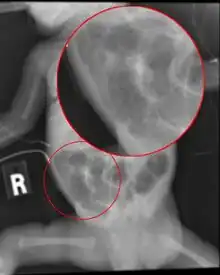

Necrotizing enterocolitis radiograph[2]